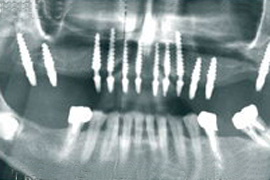

Сначала пациенту проводится диагностика потом компьютерная томограмма. Данные исследования импортируются в специальную компьютерную программу NobelGuide™ –революционную систему планирования лечения и установки имплантатов, позволяющую решить проблему отсутствия зубов безопасно и в кратчайшие сроки.

С ее помощью врач исследует строение челюстно-лицевой области пациента в режиме 3D c показом мельчайших анатомических подробностей, что позволяет с высочайшей точностью спланировать весь ход будущей имплантации. Готовые данные отправляются на завод Nobel Biocare в Швецию для изготовления индивидуального хирургического шаблона, который затем приходит в нашу клинику, и по нему проводится операция со всеми теми преимуществами, о которых было сказано выше.